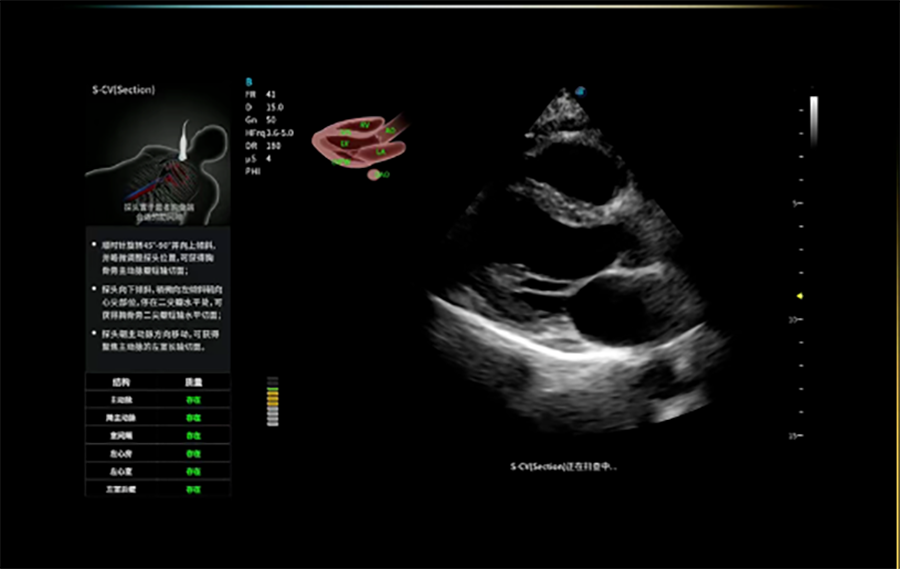

心脏自动测量

简化心血管检查操作步骤,缩短检查时间,协助医生快速完成心脏参数测算与诊断。